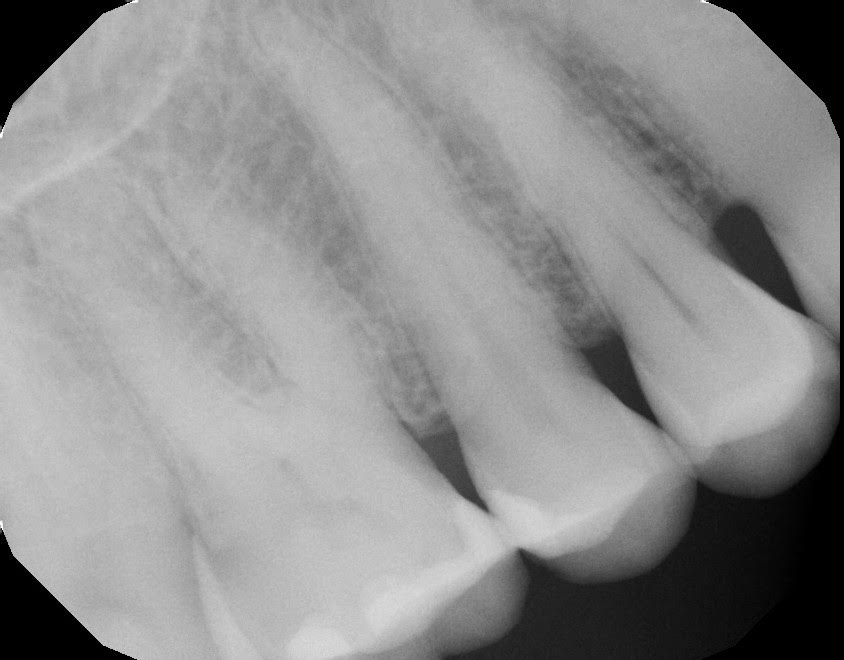

We do our usual protocol for a sensitive filling, which I’ve shared before in a past email. PA and BW show no apical pathology as well as the restoration was fairly shallow.

Here they are.

Super shallow, and no signs of apical pathology on the PAs.